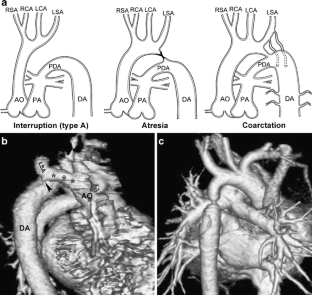

Fig. 1